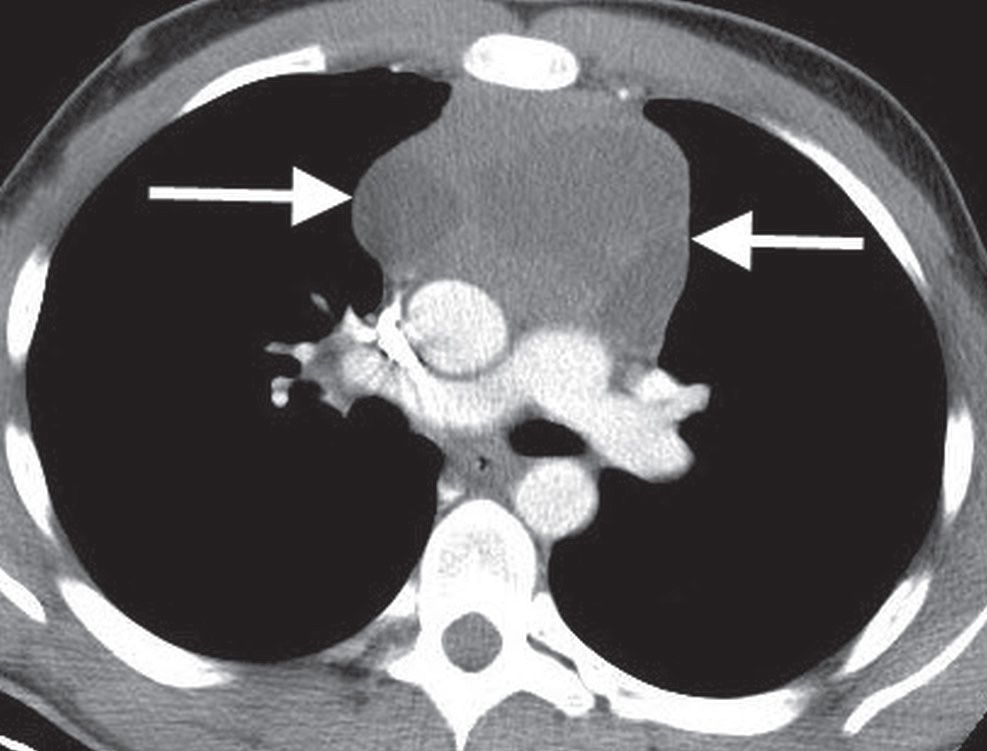

From radiologykey.com

Mediastinal Masses Radiology Key Danger Space Mediastinum Complications arising from deep neck infections that invade the danger space include mediastinitis, necrotizing fasciitis, and empyema. The danger space lies behind the true retropharyngeal space, and courses more inferiorly than the true retropharyngeal space, running into the posterior mediastinum until the level of. An infection of this space can thus spread to. The connection of the danger space to. Danger Space Mediastinum.